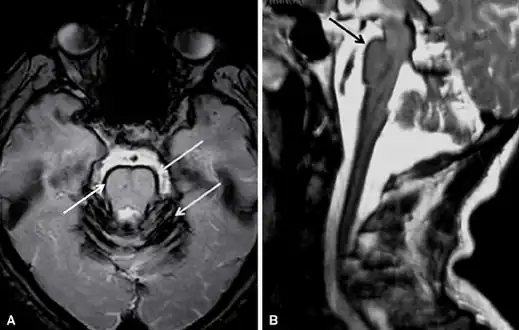

Early detection of superficial siderosis is usually via MRI. The iron deposition that is characteristic of superficial siderosis shows up as a hypointense band in affected tissues, with a characteristic rim of intensity appearing on the cerebellum; a hyperintense rim is rarely seen.[8] Taking samples of cerebrospinal fluid may also reveal siderosis through xanthochromia, elevated presence of red blood cells, high iron and ferritin concentrations, and elevated levels of the proteins Tau, amyloid beta (Aβ42), neurofilament light chain (NFL), and glial fibrillary acidic protein (GFAP), but the CSF is sometimes normal.[10] Detection is complicated by the fact that superficial siderosis is a rare disease and is not well described in neurological texts, so it may go unnoticed until noticeable symptoms appear.[11]